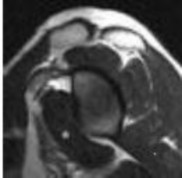

3. # Figure 5 shows the MRI scan of a 35-year-old woman with shoulder pain. What is the most likely diagnosis?

DISCUSSION: The MRI scan shows a coronal oblique view of a partial-

thickness bursal surface supraspinatus tear. Partial-thickness rotator cuff tears are a common cause of shoulder pain, with articular-sided tears two to three times more common than bursal-sided tears. The articular surface of the supraspinatus is intact in this image; therefore, no partial articular or full-thickness tear exists. The superior labrum is seen at the top of the glenoid with no tear. Internal impingement affects the articular surface of the rotator cuff in abduction and external rotation, causing labral tearing and partial articular-sided rotator cuff tears. The Preferred Response to Question # 5 is 3.